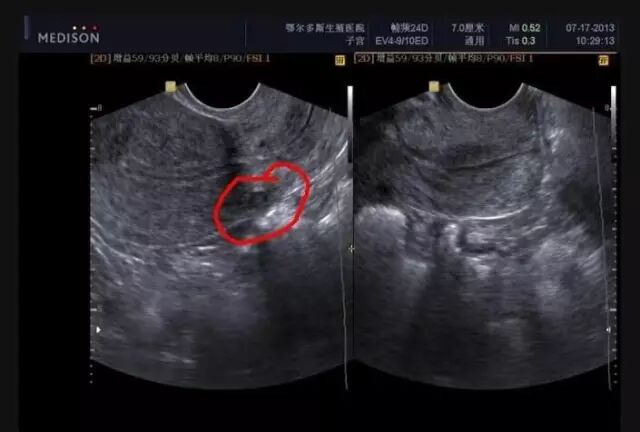

到医院一查,

这隆起的腹部竟然——全!是!子!宫!肌!瘤!而且,足!足!有!36!个!之!多!

小黄的母亲才带着她到医院检查,结果发现小黄竟有子宫肌瘤但取瘤的同时,必须切除子宫,这让未婚的小黄非常绝望。眼看肚子越来越大,走在路上如同7个月的孕妇,常被人指指点点,也引来同学和朋友背后的议论,小黄不得不请假,四处求诊。